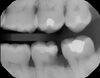

Well-defined apical radiolucency with loss of lamina dura – diagnosis?

• Periodontitis periapicalis chronica granulomatosa

• (chronic granulomatous apical periodontitis).

• Treatment: RCT or extraction

Small localised apical radiolucency confined to the apex – diagnosis?

• Periodontitis periapicalis chronica granulomatosa localisata

• (localised chronic granulomatous apical periodontitis).

* Periodontitis periapicalis chronica granulomatosa * (Chronic granulomatous apical periodontitis) → Well-defined apical radiolucency, loss of lamina dura

* Periodontitis periapicalis chronica granulomatosa localisata * (Localised chronic granulomatous apical periodontitis) → Small, confined apical radiolucency